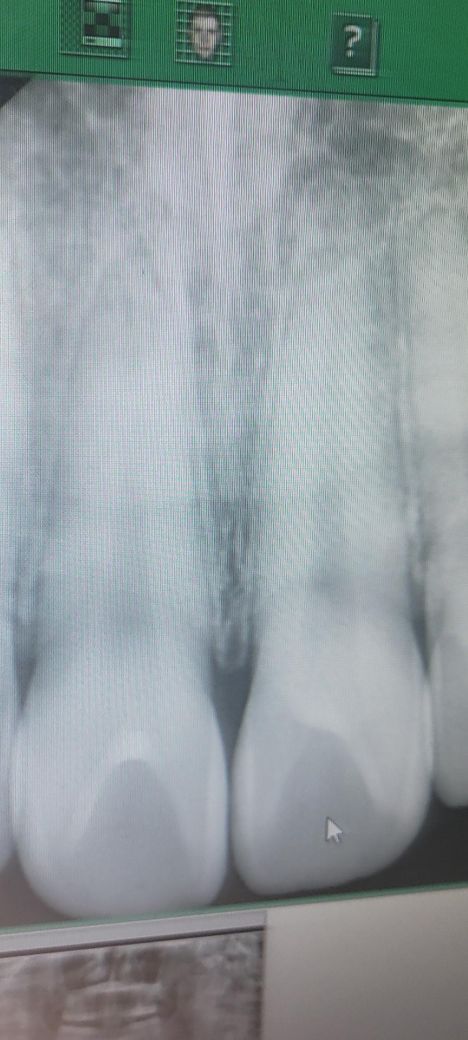

x-ray 사진에서는 정상적인 치아 소견으로 보입니다. 피곤하거나 잇몸이 들뜨면 약간 흔들거리는 느낌이 일시적으로 올 수도 있습니다.

엑스레이 상으로 앞니는 문제가 잇어 보이는건 없는거 같습니다. 크게 걱정은 안하셔도 될것같습니다.

위 사진 하나로는 판별하기는 어렵지만 특별히 문제가 보이지는 않습니다. 너무 신경안쓰시는 게 좋아보입니다.

엑스레이 사진상 치아뿌리 부분이 보이지 않아 정확한 평가가 불가능합니다. 다만, 치아의 생리적인 동요도(움직임)이 존재하니 약간 흔들리는 정도는 괜찮습니다.

원래 치아는 자연동요도가 있고 특히 기상직후 약간 느끼질정도로 움직임이 있습니다 다만 엑스레이 사진상 오른쪽 앞니 아주 미약하게 뿌리끝 염증이 보이는 것 같기도 하며 이로인한 동요일수도 있습니다